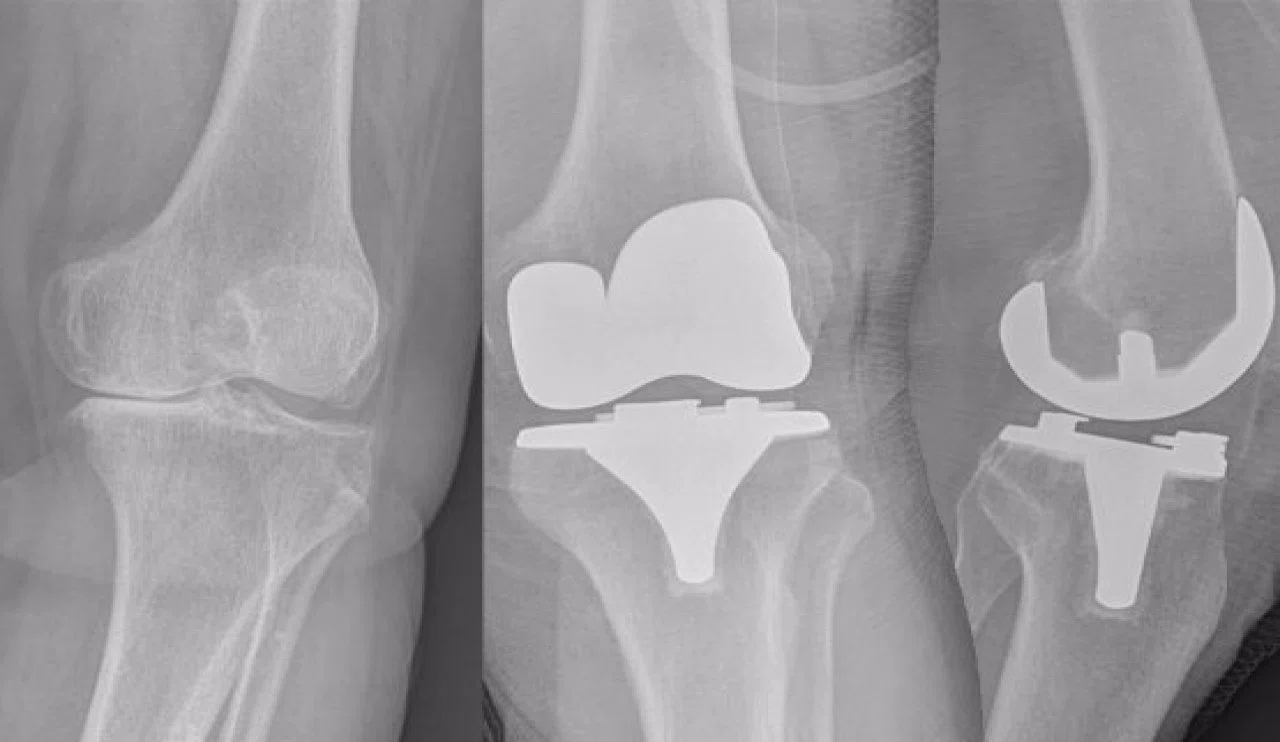

Röntgen filmleri, kemik ve dokuların görüntülerini oluşturmak için X-ışınları kullanır. Bebeklerin diz kapaklarında ise kemik yerine kıkırdak dokusu bulunur. Kıkırdak dokusu, X-ışınlarını kemik kadar yoğun emmediği için röntgen filminde görünmez.

Bebeklerin diz kapakları genellikle 3-4 yaşına kadar kemikleşmez. Bu yaştan önce diz kapakları röntgen filminde görünmese de, bu durum herhangi bir sağlık sorununa işaret etmez. Doktorlar, bebeğin diz eklemini değerlendirmek için diğer görüntüleme yöntemlerini kullanabilirler.